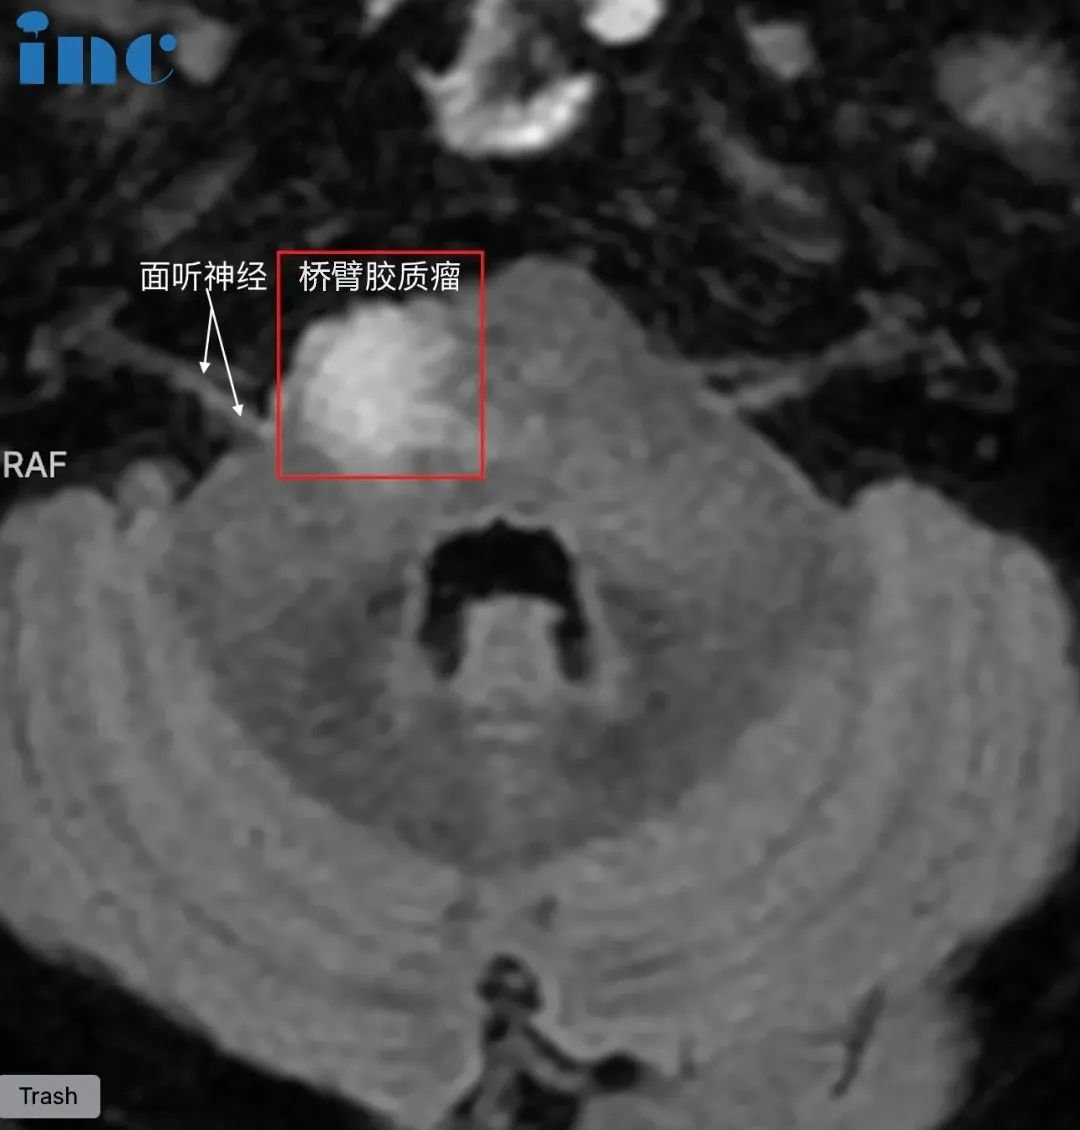

脑干-桥臂胶质瘤长大,三根重要神经包绕肿瘤

脑干桥臂位置,肿瘤还被面神经,滑车神经,听神经等重要神经包绕,手术难度之大不言而喻。巴教授是他们然后的希望。2023年9月29日,中秋节当天,巴教授为韩先生成功手术。